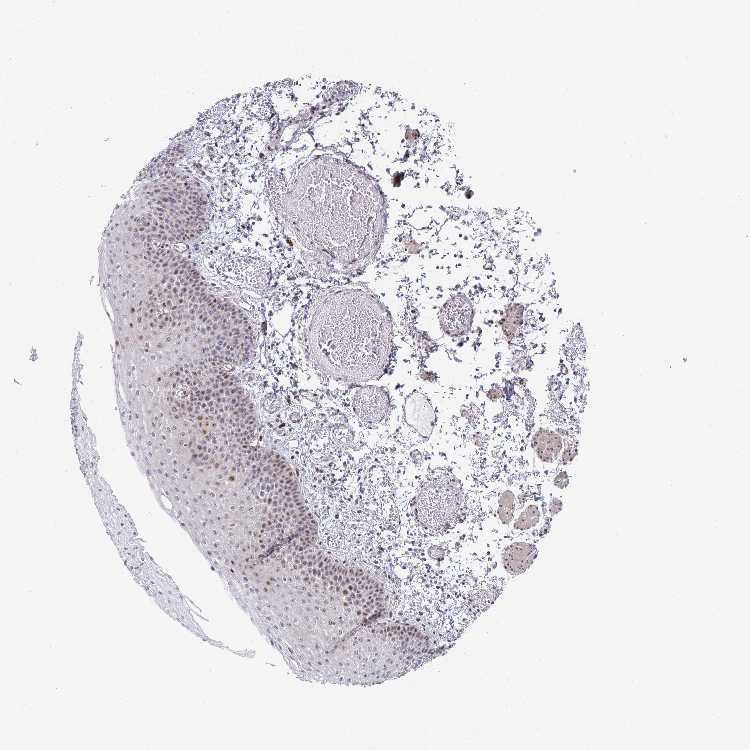

ESOPHAGUS - Antibody stainingi

Antibody staining in the annotated cell types in the current human tissue is reported as not detected, low, medium, or high, based on conventional immunohistochemistry profiling in selected tissues. This score is based on the combination of the staining intensity and fraction of stained cells.

Each image is clickable and will lead to virtual microscopy that enables deeper exploration of all samples and also displays staining intensity scores, fraction scores and subcellular localization as well as patient and tissue information for each sample.

Antibody HPA052936

Squamous epithelial cells Low